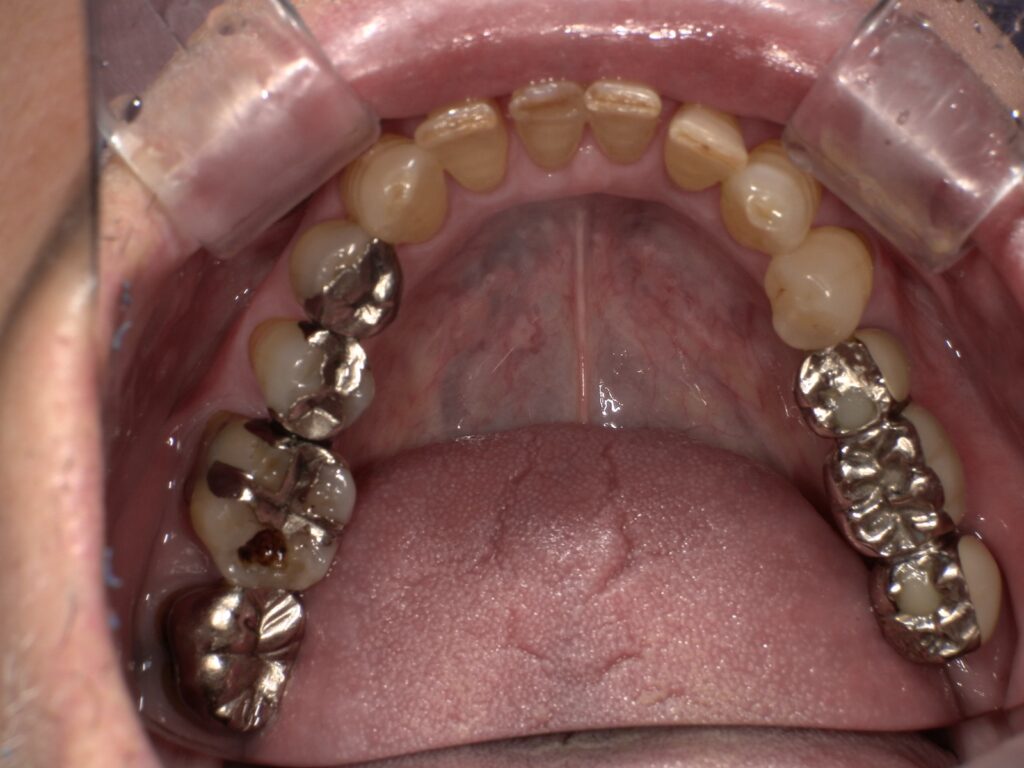

初診時のパノラマレントゲン写真です。

左上の6番7番の咬合痛及び左下のブリッジの動揺が主訴で来院されました。左上6番7番は歯根破折、左下5番8番はかなり動揺しておりいずれも保存不可と判断し、抜歯をした後インプラント治療をご希望されました。